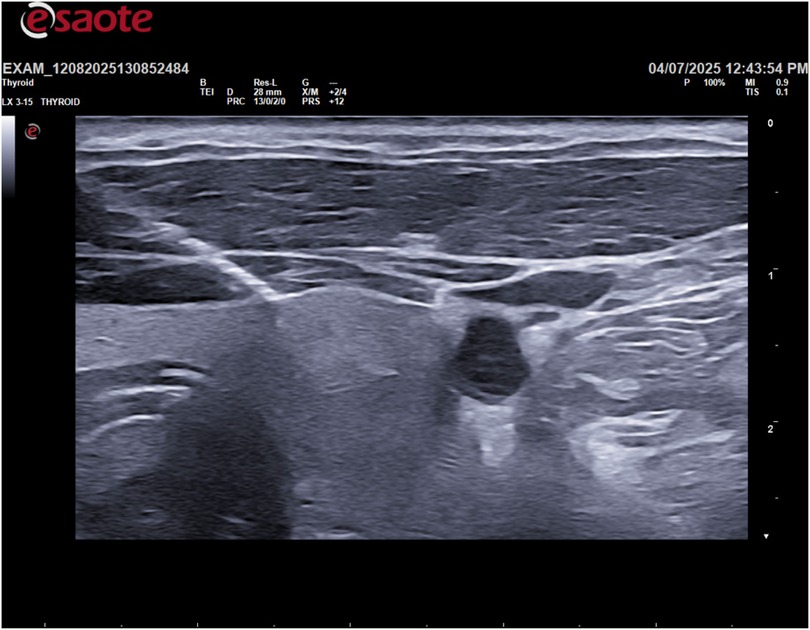

This study describes a single case report of a 55-year-old male with a family history of papillary thyroid carcinoma. The patient presented with an asymptomatic thyroid nodule detected on routine ultrasound. All clinical and imaging data were collected from the patient's medical records. The patient provided informed consent for the use of his data for research purposes. A thyroid ultrasound was performed using a high-frequency linear transducer (10–14 MHz). The ultrasound scan revealed a large, cystic lesion in the inferior portion of the thyroid gland with the following dimensions: AP 52.1 mm, Transverse 55.3 mm, and Sagittal 66.8 mm, for a calculated volume of 93.2 ml (Figure 1).

Figure 1

Ultrasound image with color Doppler of a thyroid nodule. Measurements show dimensions: anterior-posterior 52.1 mm, transverse 55.3 mm, sagittal 61.8 mm. Nodule volume is 93.2 ml. Color indicators suggest blood flow.

Figure 1. Sagittal diameter and volume of the lesion.